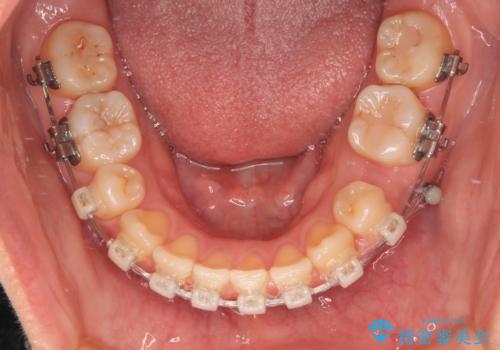

- 矯正装置

- クリアブラケット

- 1年10ヶ月

上下前歯のズレは舌の突出癖による影響も大きいと考えられたたため、舌のトレーニングをしっかりと行っていただきました。